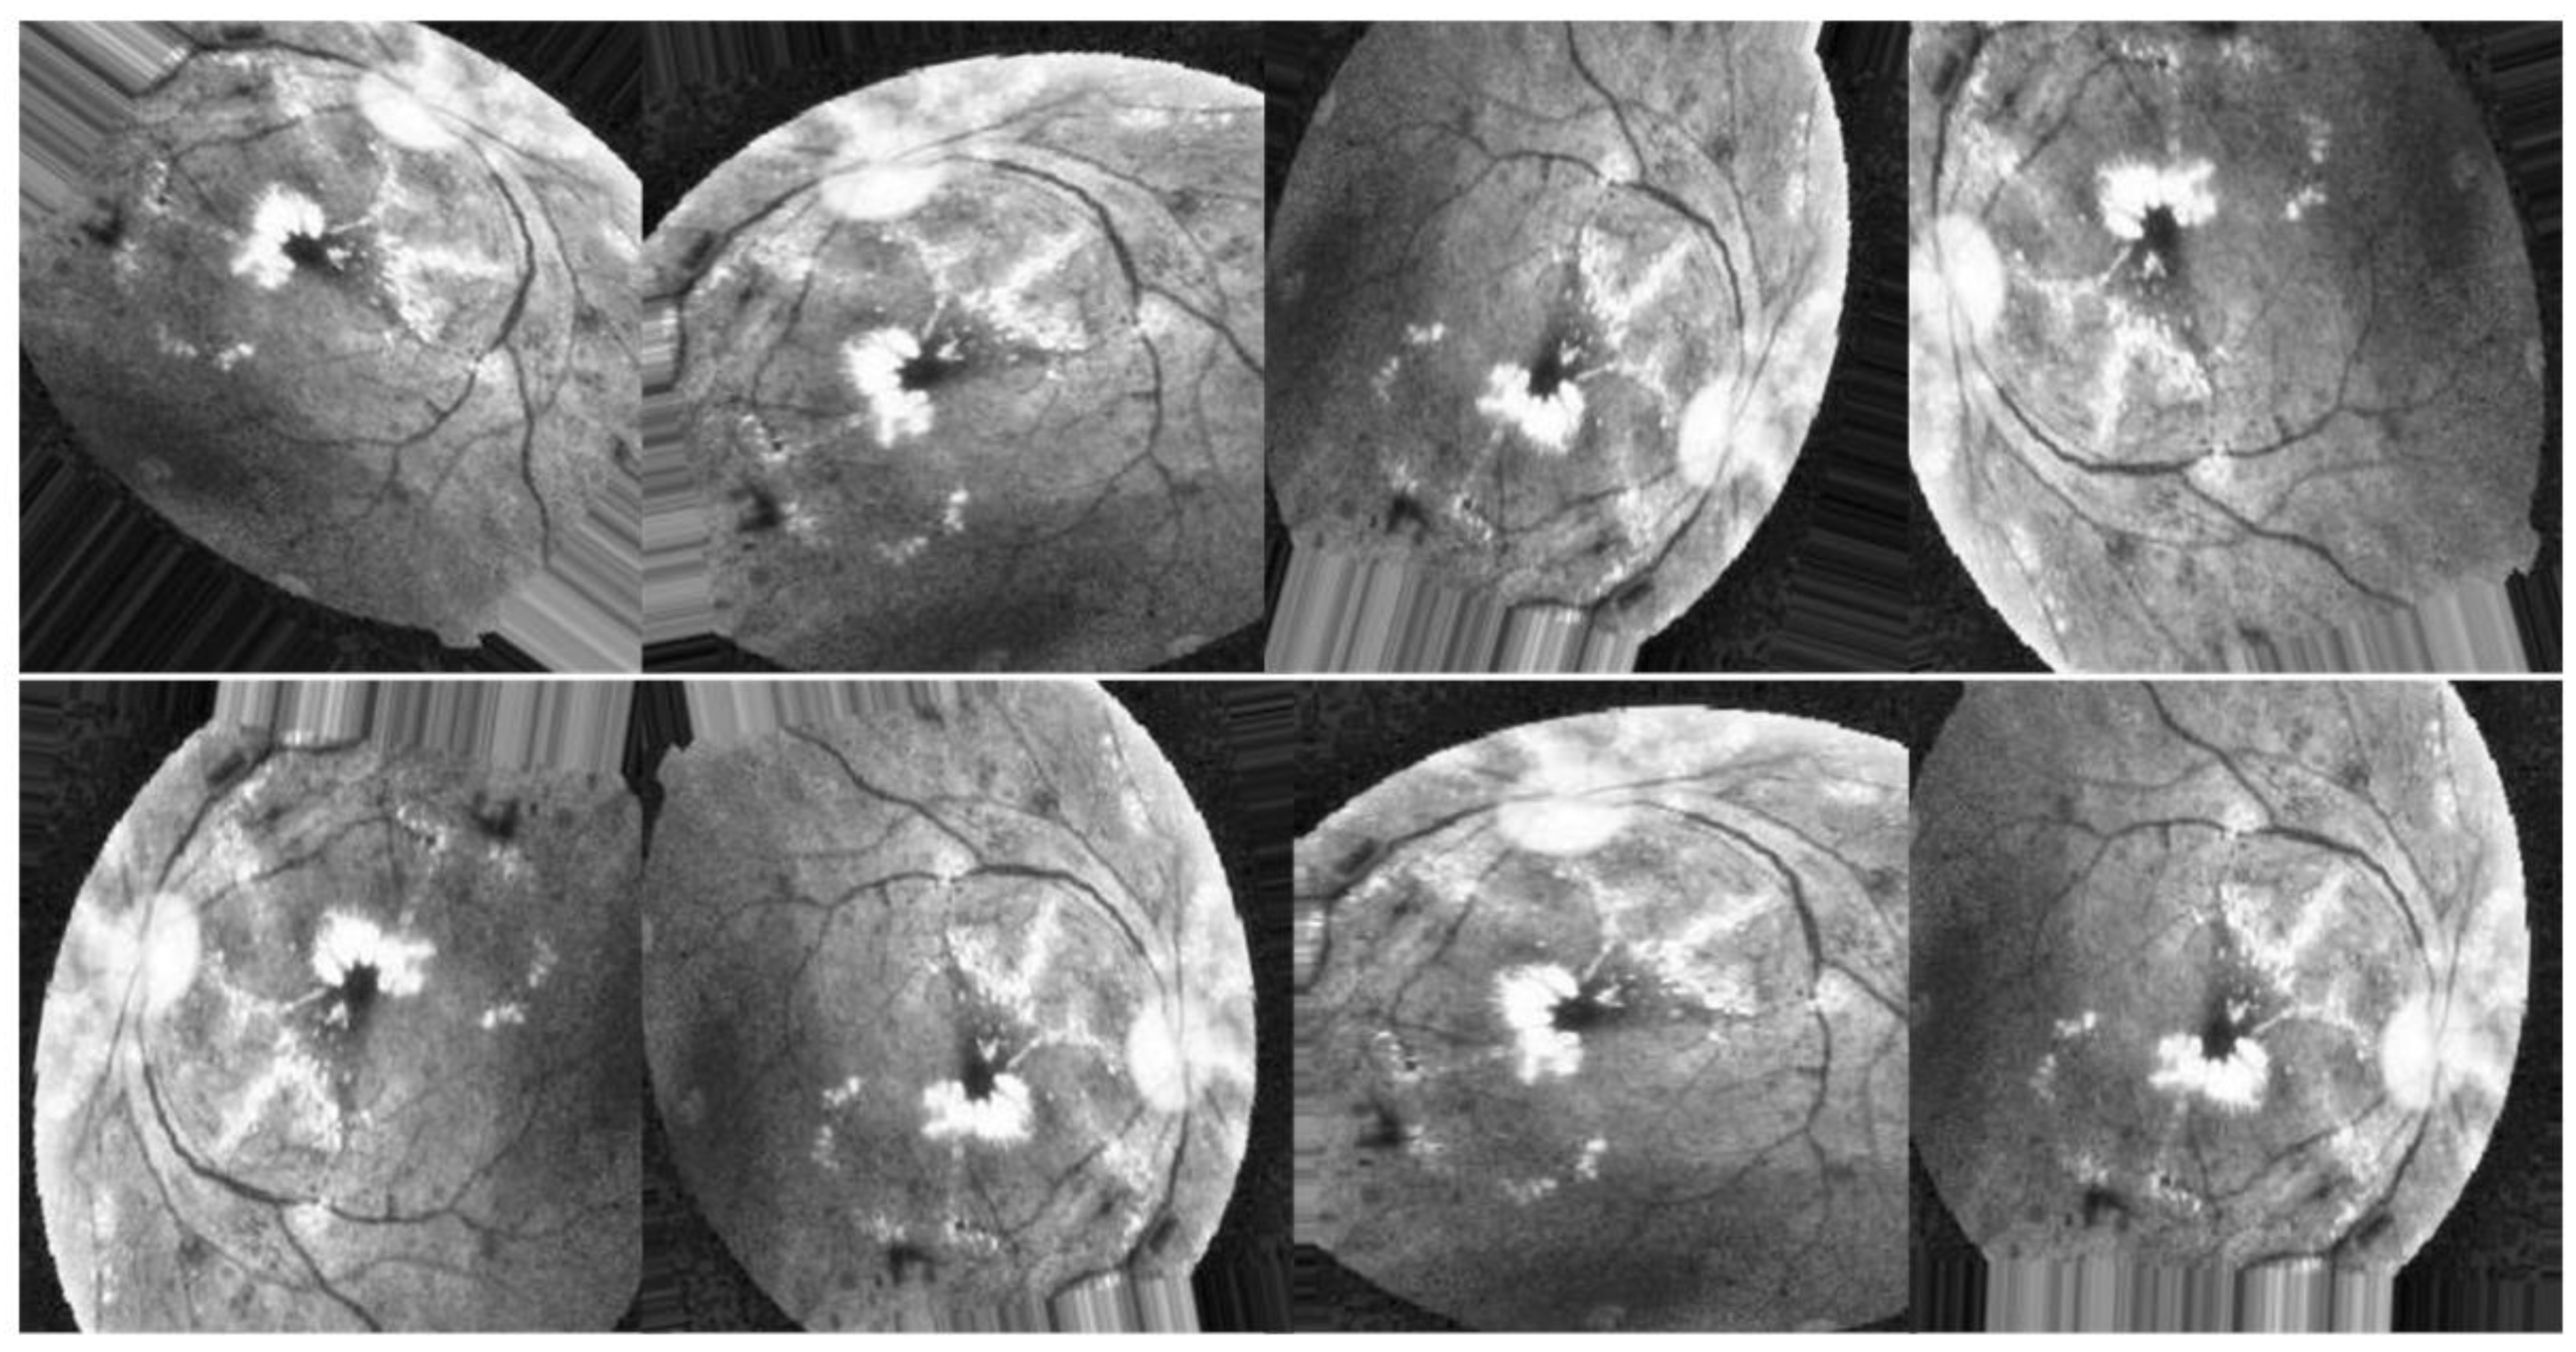

Scenario III

Finally, in the third scenario, augmentation techniques are applied to the enhanced images utilizing HIST, CLAHE, and ESRGAN, respectively, as depicted in Figure 10.

Figure 10. Examples of augmenting the same image with different methods (HIST + CLAHE + ESRGAN).